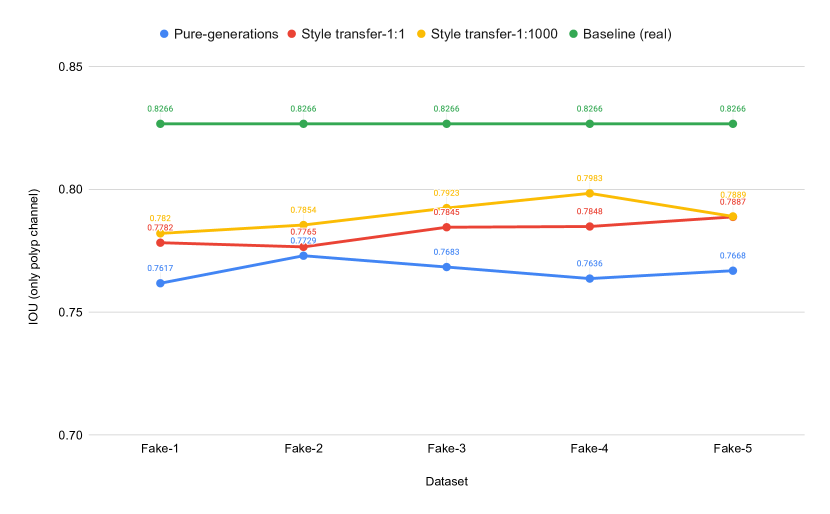

Table 2 shows the results collected from the UNet++ segmentation experiments for the baseline experiment and the experiments conducted with synthetic data, which contains pure generated synthetic data and style transferred data using and . Differences in IOU scores of these three experiments are plotted in Fig 9 for easy comparison.

| Train data | ST (cw:sw) | Dice loss | IoU | f-score | Accuracy | Recall | Precision |

|---|---|---|---|---|---|---|---|

| REAL | NA | 0.1123 | 0.8266 | 0.8882 | 0.9671 | 0.8982 | 0.9161 |

| FAKE-1 | No ST | 0.1645 | 0.7617 | 0.8357 | 0.9531 | 0.8630 | 0.8793 |

| 1:1 | 0.1504 | 0.7782 | 0.8500 | 0.9572 | 0.8672 | 0.8917 | |

| 1:1000 | 0.1473 | 0.7820 | 0.8530 | 0.9591 | 0.8624 | 0.9005 | |

| FAKE-2 | No ST | 0.1549 | 0.7729 | 0.8453 | 0.9561 | 0.8692 | 0.8895 |

| 1:1 | 0.1550 | 0.7765 | 0.8453 | 0.9575 | 0.8729 | 0.8852 | |

| 1:1000 | 0.1477 | 0.7854 | 0.8525 | 0.9609 | 0.8647 | 0.9038 | |

| FAKE-3 | No ST | 0.1610 | 0.7683 | 0.8391 | 0.9556 | 0.8568 | 0.8945 |

| 1:1 | 0.1475 | 0.7845 | 0.8525 | 0.9585 | 0.8723 | 0.8936 | |

| 1:1000 | 0.1408 | 0.7923 | 0.8593 | 0.9629 | 0.8693 | 0.9078 | |

| FAKE-4 | No ST | 0.1649 | 0.7638 | 0.8352 | 0.9525 | 0.8669 | 0.8780 |

| 1:1 | 0.1464 | 0.7848 | 0.8537 | 0.9594 | 0.8713 | 0.8921 | |

| 1:1000 | 0.1370 | 0.7983 | 0.8630 | 0.9636 | 0.8653 | 0.9185 | |

| FAKE-5 | No ST | 0.1654 | 0.7668 | 0.8345 | 0.9563 | 0.8565 | 0.8919 |

| 1:1 | 0.1453 | 0.7887 | 0.8547 | 0.9610 | 0.8703 | 0.9000 | |

| 1:1000 | 0.1458 | 0.7889 | 0.8543 | 0.9620 | 0.8527 | 0.9211 |

is the short form of weights ratio. Baseline performance values of using real data are represented using bold text. Moreover, the best performance values of using fake data are marked using bold text. FAKE-N represents a number of images generated from a single image using our model, i.e., FAKE-1 to represent one fake image, FAKE-2 to represent two fake images per real image, etc..